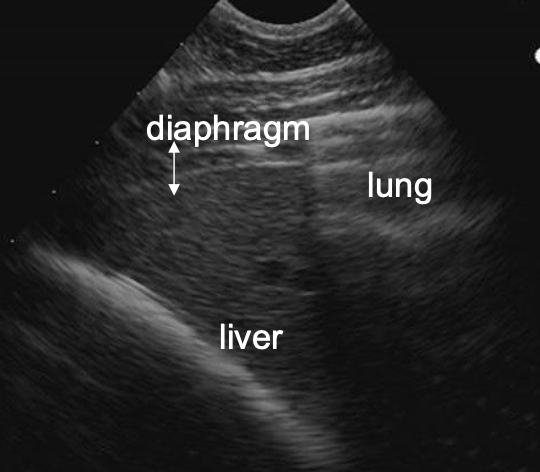

ultrasound

must know normals! (architecture, expected size, comparison to spleen)

where is the liver located on the right side of the horse?

6th-15th intercostal space

ventral to lung (usually ends at costochondral junction)

may not be visible in geriatric horses (right lobes atrophy as horses age)

what is the normal appearance of the liver on ultrasound?

-uniform

-sharp edges

-darker than spleen (left side)

-ends at or before costochondral junction (dont confuse with peritoneal fat)

-anechoic vessels visible

-no obvious biliary channels

-no shadowing structures